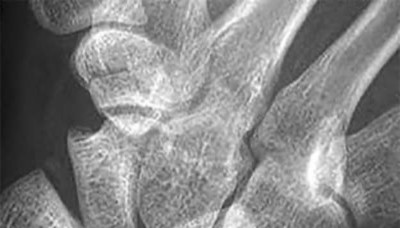

A 20-year-old park ranger trips and falls onto his right wrist with the wrist in extension and pronation. The local urgent care orders both radiographs and a CT, which you review and determine to be normal. The patient complains of ulnar-sided wrist pain. On exam, his tenderness is localized to the fovea. Ulnar deviation also causes him pain. There is no snapping sensation with wrist supination, flexion, and ulnar deviation. He otherwise has 5/5 strength to his first dorsal interosseous muscle with 4mm static two-point discrimination on the ulnar side of the 4th digit. Which of the following injuries is most likely responsible for his symptoms and exam?